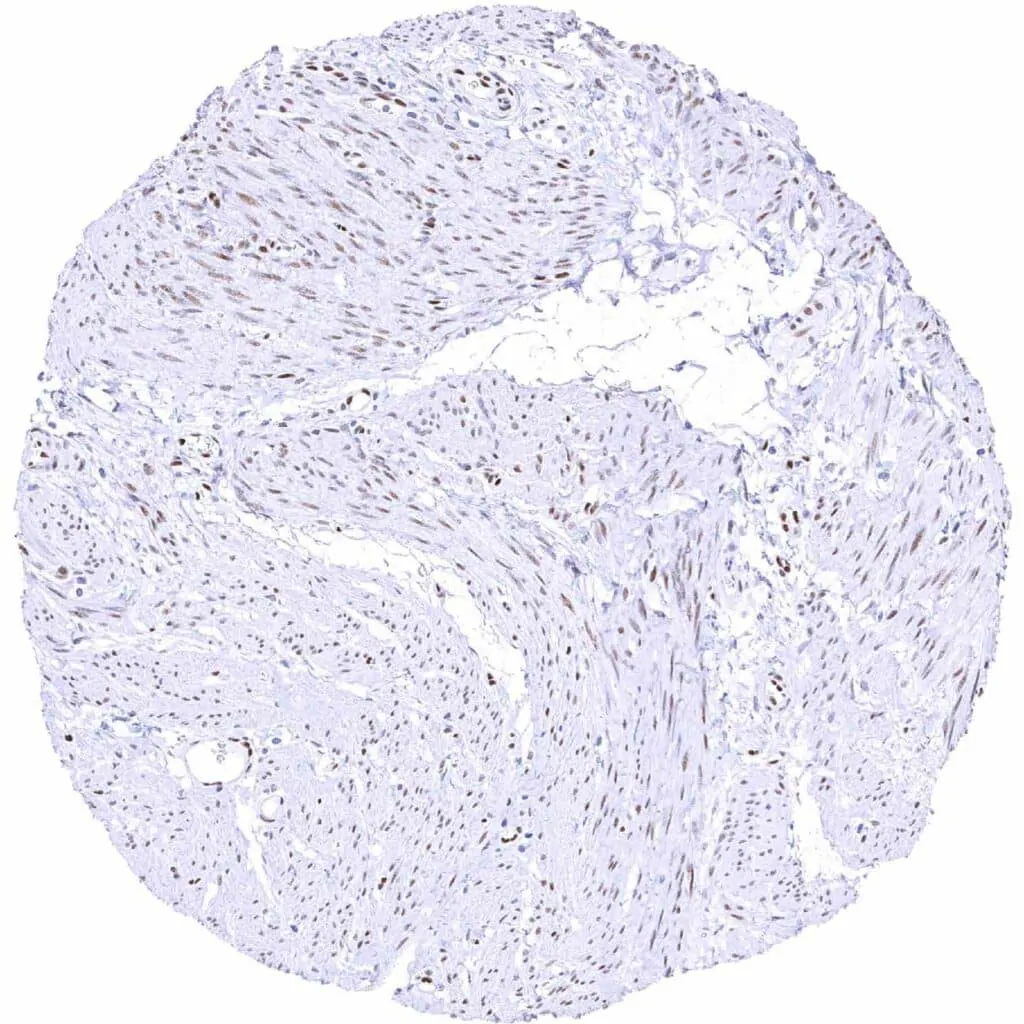

Uterus, myometrium – Weak to moderate TLE1 positivity of smooth muscle cells